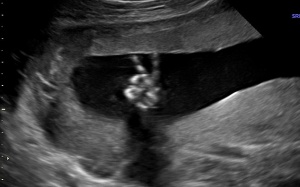

Câu hỏi: Chào bác sỹ! Em có thai được 15 tuần. Khi đi khám thai, bác sỹ kết luận cổ tử cung hơi ngắn. Cổ tử cung ngắn có ảnh hưởng tới thai nhi không? Mong bác sỹ tư vấn giúp em! Em cảm ơn...